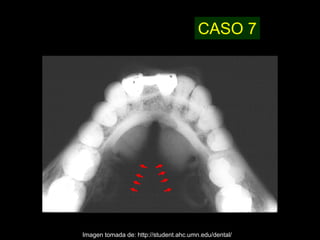

CASO 7

Imagen tomada de: http://student.ahc.umn.edu/dental/

CASO 7 Imagen tomadade: http://student.ahc.umn.edu/dental/